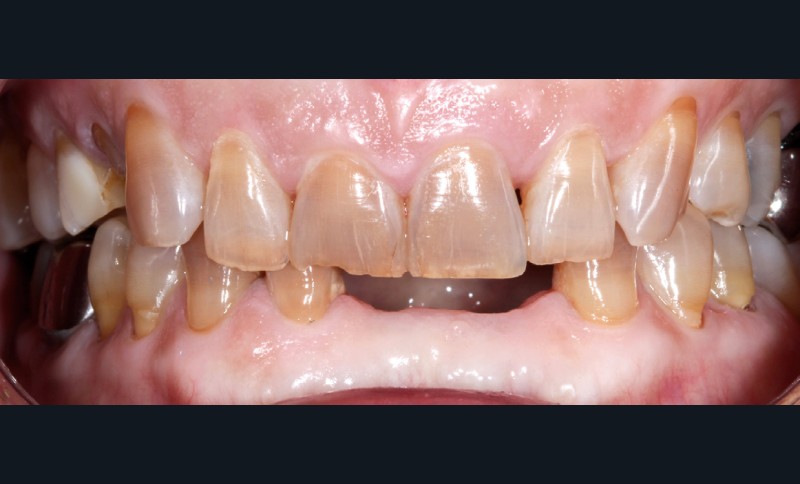

– Traumatismes (fig. 5a, b).